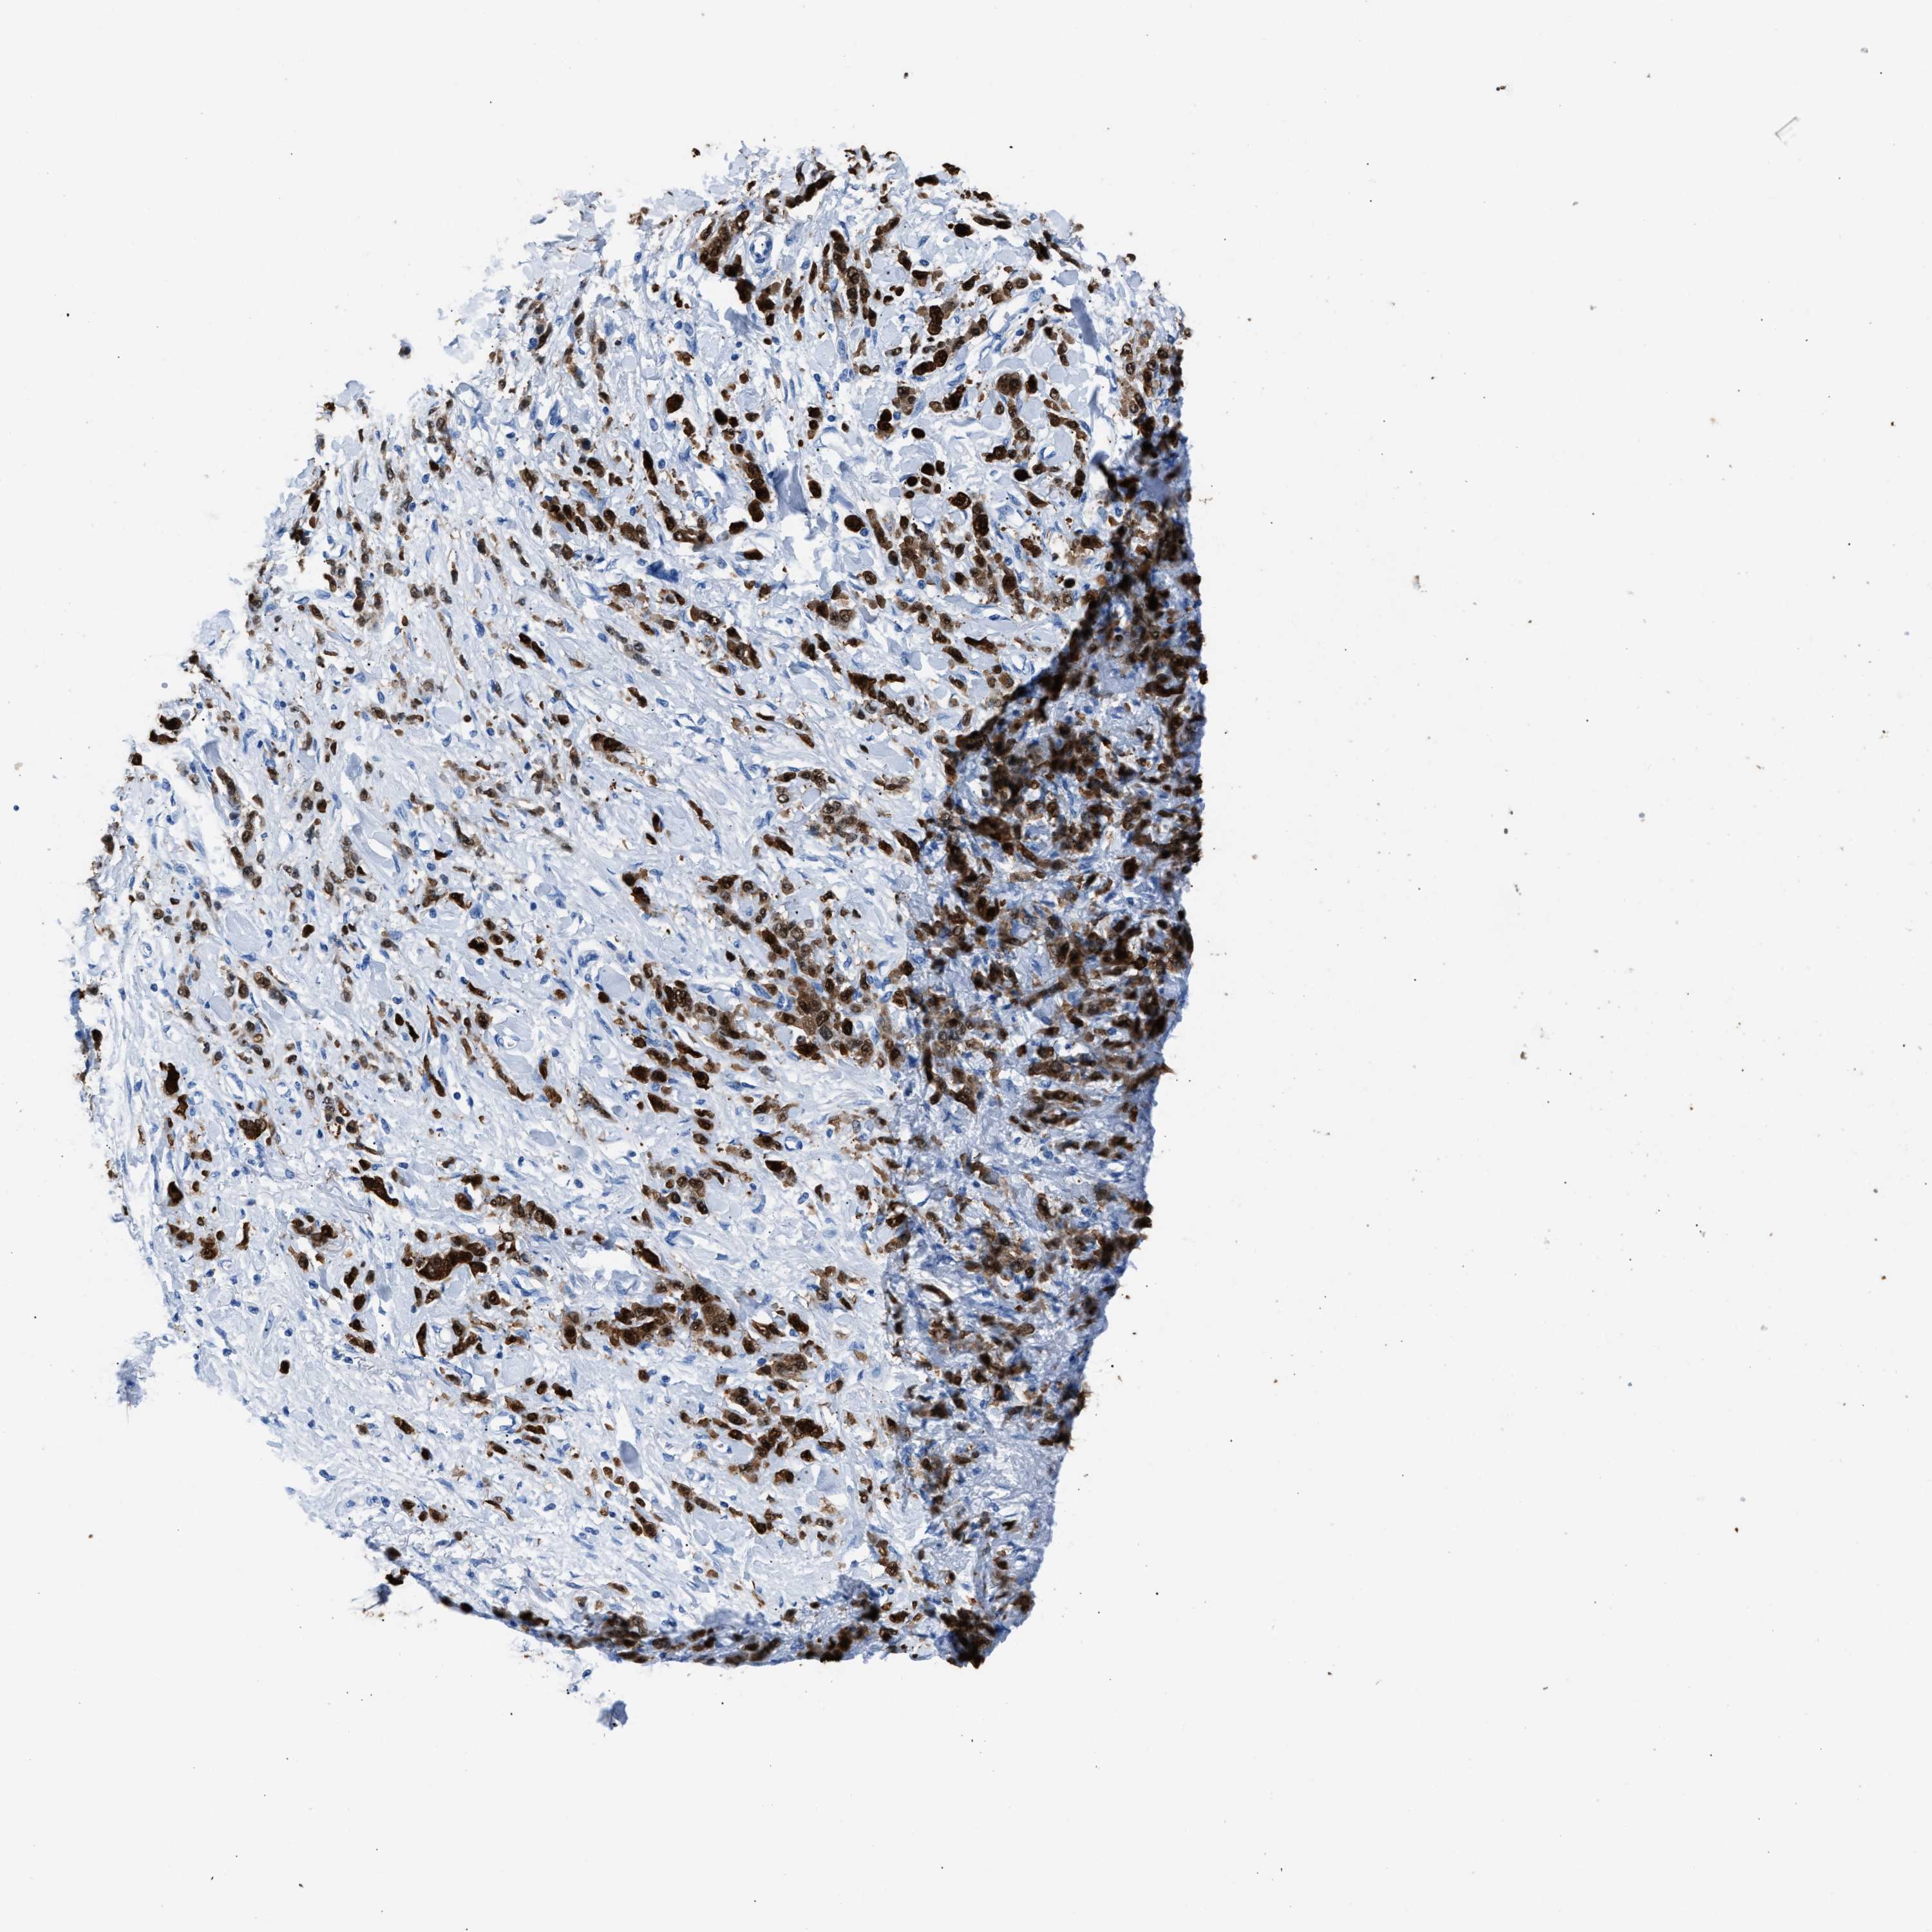

STOMACH CANCER - Protein expressioni

A mouse-over function shows sample information and annotation data. Click on an image to view it in a full screen mode. Samples can be filtered based on level of antibody staining by selecting one or several of the following categories: high, medium, low and not detected. The assay and annotation is described here.

Note that samples used for immunohistochemistry by the Human Protein Atlas do not correspond to samples in the TCGA dataset.

Antibody stainingi

Antibody staining in the annotated cell types in the current human tissue is reported as not detected, low, medium, or high, based on conventional immunohistochemistry profiling in selected tissues. This score is based on the combination of the staining intensity and fraction of stained cells.

Each image is clickable and will lead to virtual microscopy that enables deeper exploration of all samples and also displays staining intensity scores, fraction scores and subcellular localization as well as patient and tissue information for each sample.

Antibody HPA019502

Staining

High

Medium

Low

Not detected

Intensity

Strong

Moderate

Weak

Negative

Quantity

>75%

75%-25%

<25%

None

Location

Nuclear

Cytoplasmic/membranous

Cytoplasmic/membranous,nuclear

Adenocarcinoma, NOS